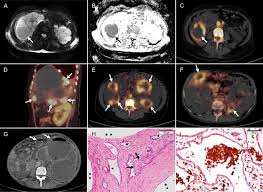

Scielo Brasil Cyst Infection In Hospital Admitted Autosomal Dominant Polycystic Kidney Disease Patients Is Predominantly Multifocal And Associated With Kidney And Liver Volume Cyst Infection In Hospital Admitted Autosomal Dominant Polycystic Kidney